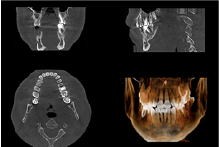

インプラント

最初にインプラントが必要な歯の数、患者様の骨がどのような状態にあるのかを診察し治療方針を決定します。その後手術で埋め込んだネジが骨にくっつくのを3ヶ月位待ちます。

骨とインプラントがしっかりと繋がったことが確認できたら型を取って人工の歯を取り付けます。

上顎の骨は下顎と比較して柔らかいので半年くらい骨と繋がるのを待つ必要があるため治療期間は長くなります。

インプラントは自分の歯と同様に噛めるようになるため歯をなくしてしまった患者様にはより良い治療の選択肢といえるでしょう。

ただし患者様の顎の骨の状態によっては施すことが難しい場合がございますので、治療を検討中の患者様はまずは当院へご相談ください。